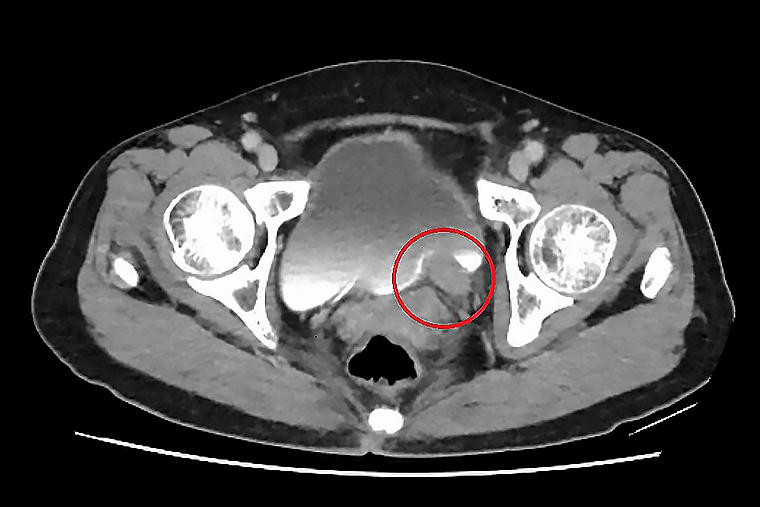

▲電腦斷層顯示,左側輸尿管末端有一顆約5公分大腫瘤。(圖/台北慈濟醫院提供)

【NOW健康 楊芷晴/新北報導】67 歲的林女士一向健康,卻在近期出現間歇性的無痛血尿,她原本以為只是小問題,至台北慈濟醫院檢查後,竟發現左側輸尿管末端長了一顆5公分的腫瘤,並造成腎水腫情形。確診為輸尿管泌尿上皮癌後,台北慈濟醫院許竣凱醫師先安排化療縮小腫瘤,再利用達文西手術切除腫瘤並重建輸尿管,成功保留腎臟功能,林女士術後追蹤至今,病情控制良好。

許竣凱醫師進一步解釋,「以林奶奶為例,其腫瘤位於下段輸尿管,在化療成效良好的情況下,只需切除病灶,再將膀胱提起與輸尿管相接,完成重建。」若經完整切除,病人的五年存活率可達9成,但仍需定期追蹤,以降低復發風險。